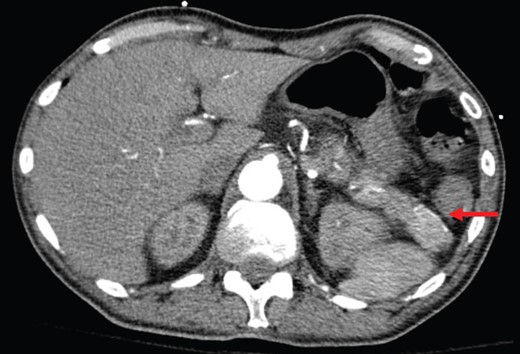

Abdominal CT shows a 2.2-cm arterial enhancing lesion (marked by red arrow) in tail of pancreas consistent with an insulinoma.